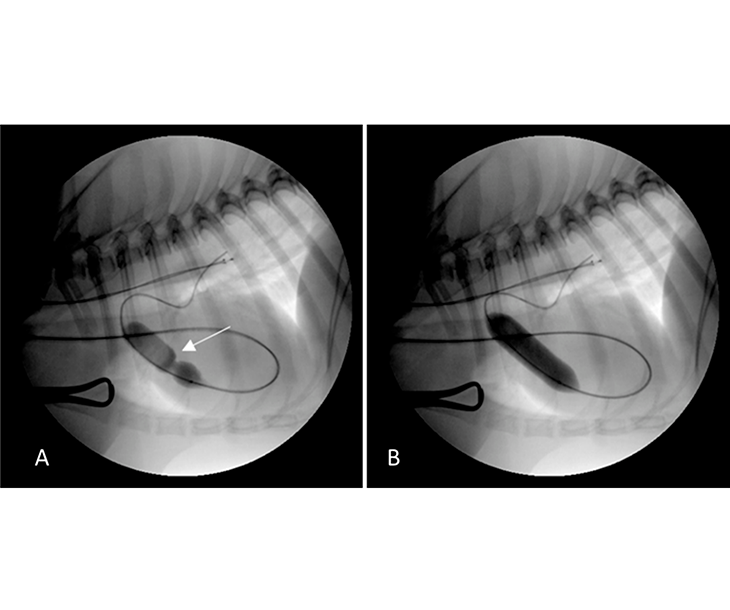

폐동맥 협착 풍선 확장술(Balloon Pulmonary Valvuloplasty)

폐동맥 협착 풍선 확장술(Balloon Pulmonary Valvuloplasty Eshms Balloon Angioplasty)은 폐동맥 혹은 폐동맥 판막의 협착을 치료하기 위한 중재적 시술입니다. 카테터를 통해 좁아진 부위에 특수 풍선을 삽입한 후, 일정 압력으로 풍선을 팽창시켜 혈관을 넓히고 혈류를 개선합니다. 전신마취 또는 진정 상태에서 시행되며, 수술적 개입 없이도 효과적으로 협착을 완화할 수 있는 최소침습적 치료법으로, 시술 시간과 회복 기간이 짧고 합병증 발생률도 낮습니다.